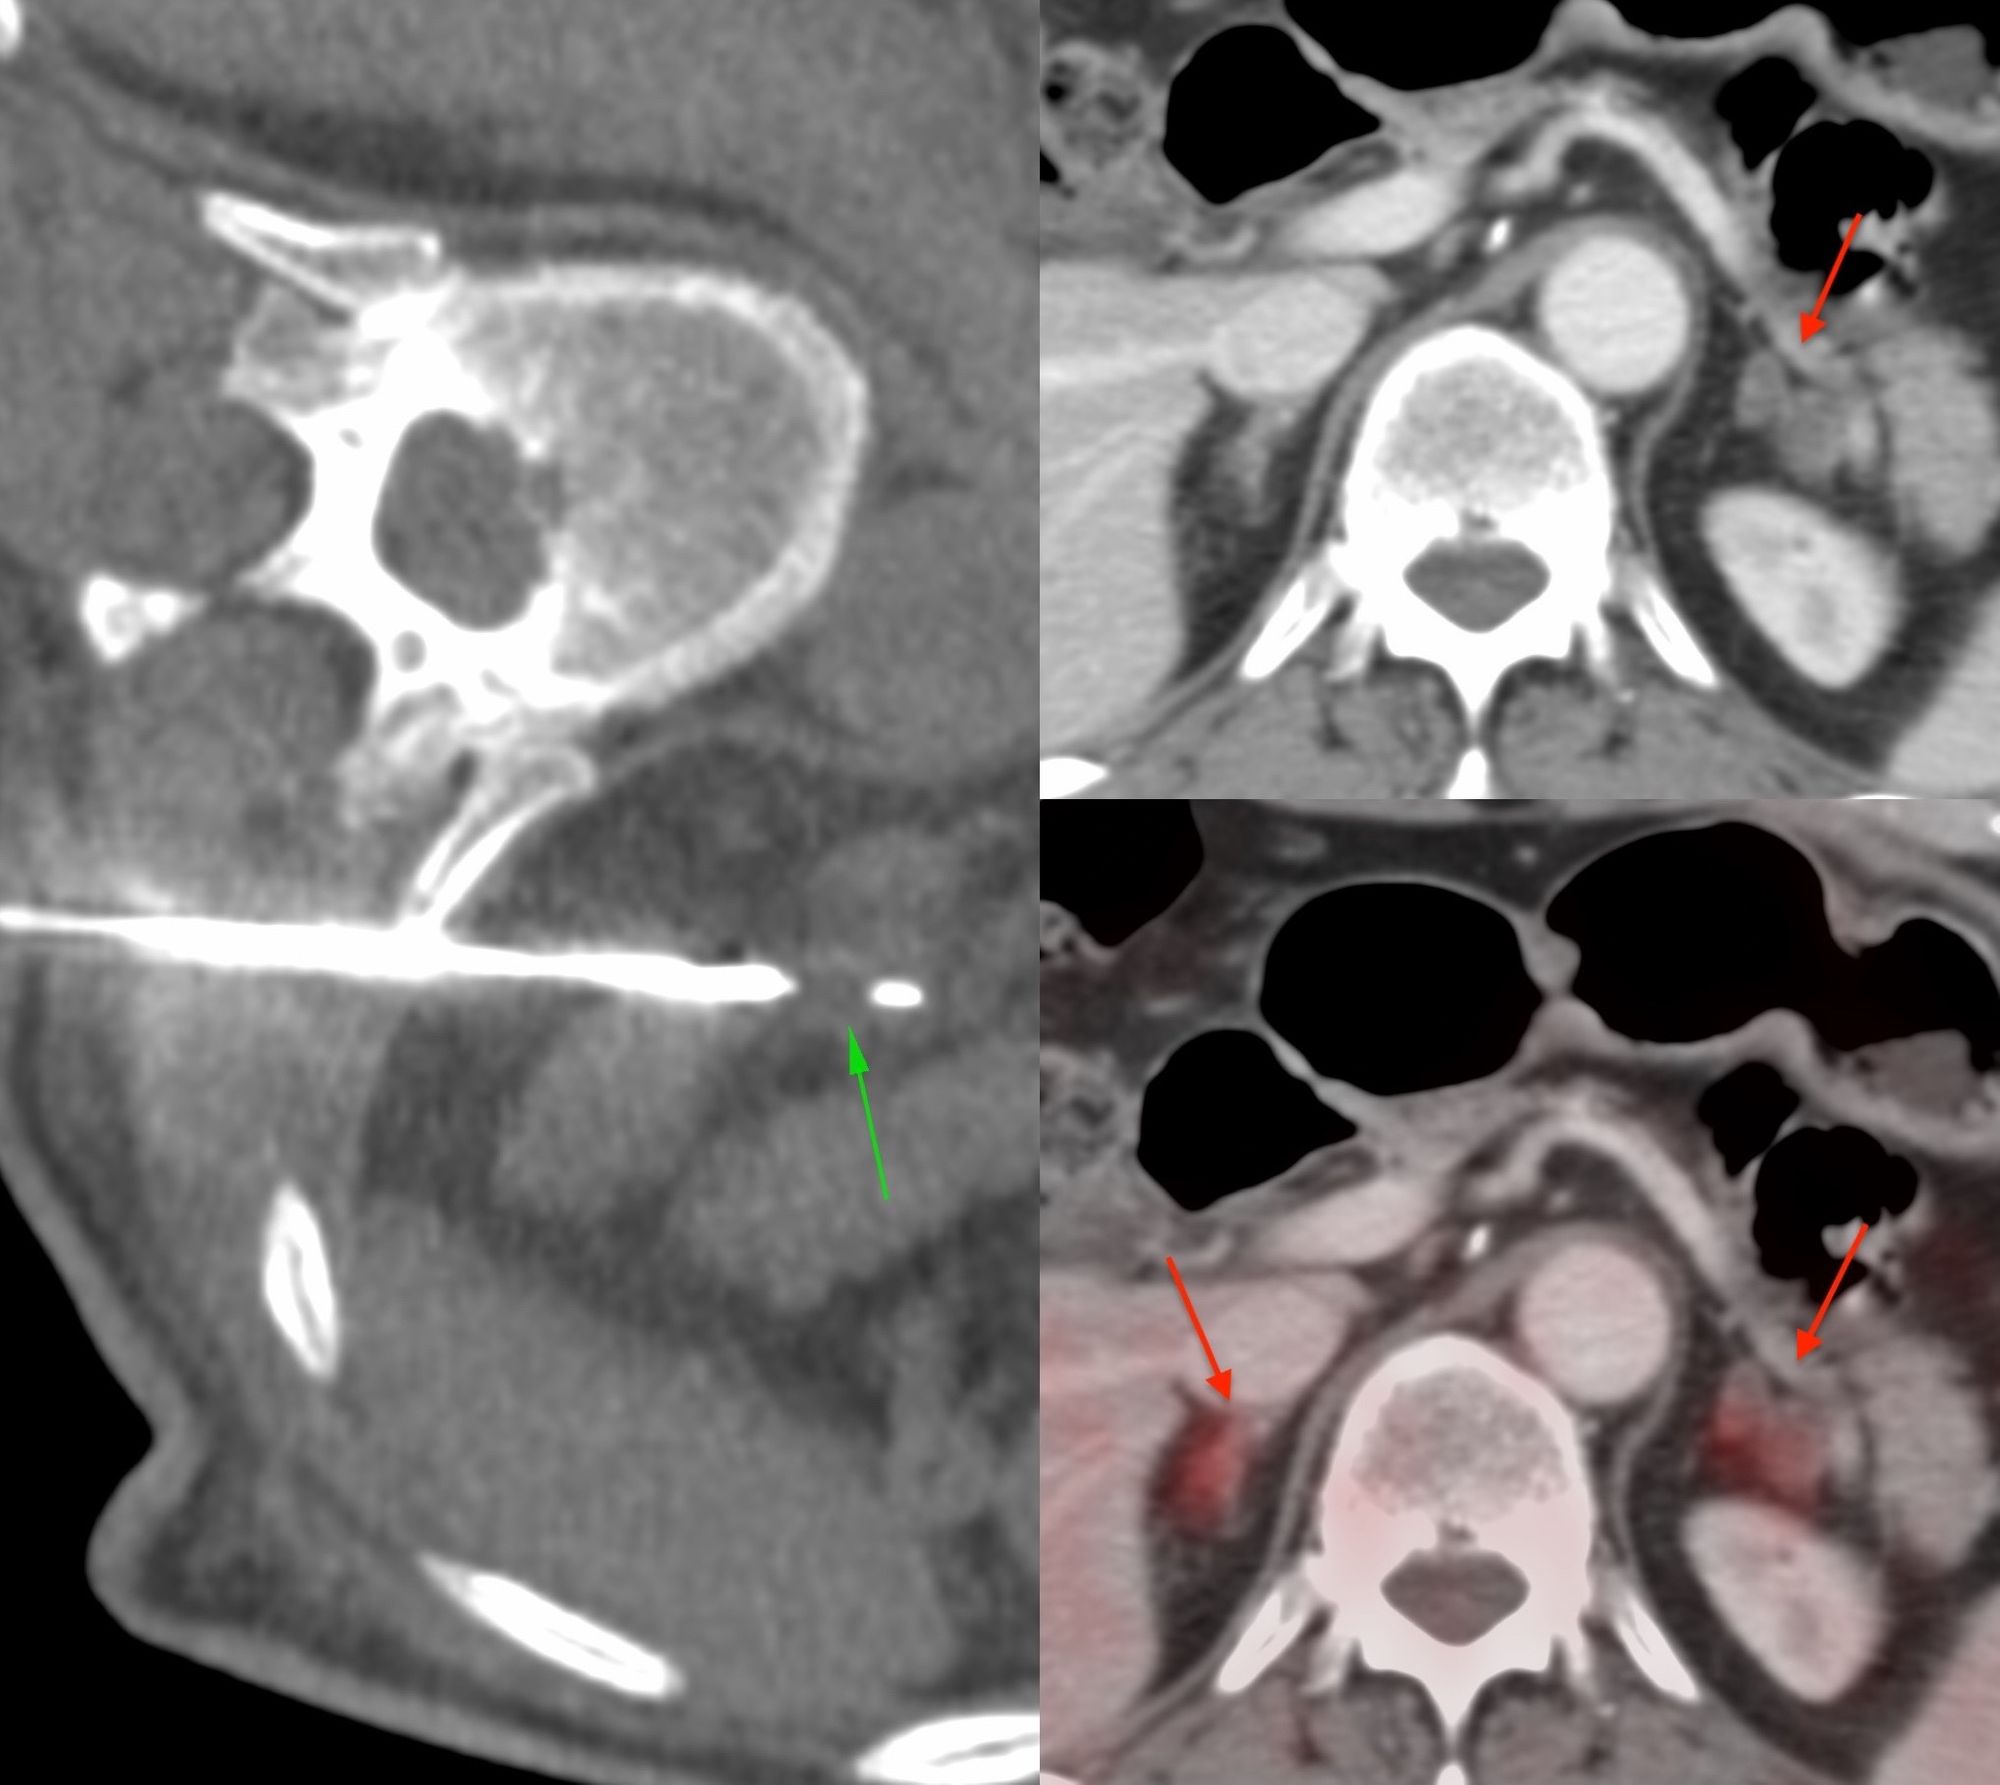

Case 19: 5.6 cm Renal Mass Biopsy